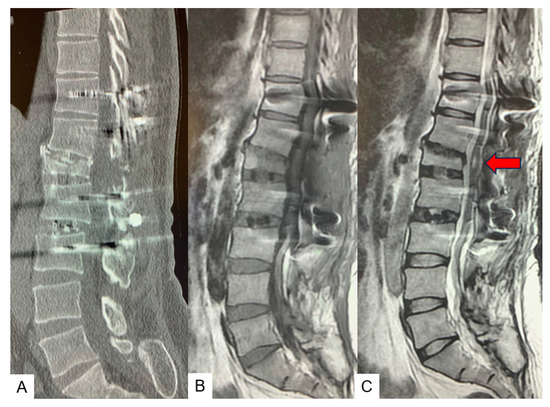

2.6. One Year Follow-Up

3. Case 2: 33-Year-Old Male, Tethered Cord Syndrome, Conventional Technique